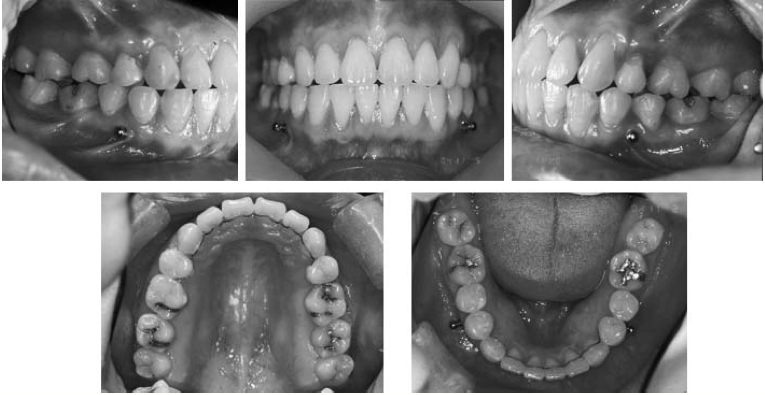

Este artigo descreve o tratamento de uma paciente do sexo feminino, com idade de 23 anos e 5 meses, com uma  má oclusão de Classe II divisão 1, que mostrou protusão anterior severa e apinhamento anterior.

Mini-Implantes ortodonticos especialmente desenhados foram colocados bilateralmente no espaço interdental entre ambos os dentes na parte superior e  inferior posteriores. Os dois primeiros molares mostraram graves lesões apicais. Portanto, o plano de tratamento consistiu de extração de ambos os primeiros pré-molares superiores e  primeiros molares inferiores, retração em massa dos seis dentes anteriores superiores, menor alinhamento anterior e protração de todos os molares inferiores.

Os C-implantes foram usados ​​como substitutos dos dentes superiores posteriores de ancoragem durante a retração anterior e como ganchos para protração molar inferior. A sobremordida e overjet ideais foram obtidas através da intrusão e retração dos seis dentes anteriores superiores para suas posições corretas.

A dentição foi corrigda usando aparelhos ortodônticos convencionais. A parte superior de C-implantes contribuiu para uma melhoria em equilíbrio facial, e os C-implantes permitiram corrigir os segundo e terceiros molares inferiores com menos efeito sobre o eixo dos dentes anteriores inferiores.

O período de tratamento ativo foi de 29 meses, e os dentes do paciente continuaram estáveis após 11 meses da finalização.